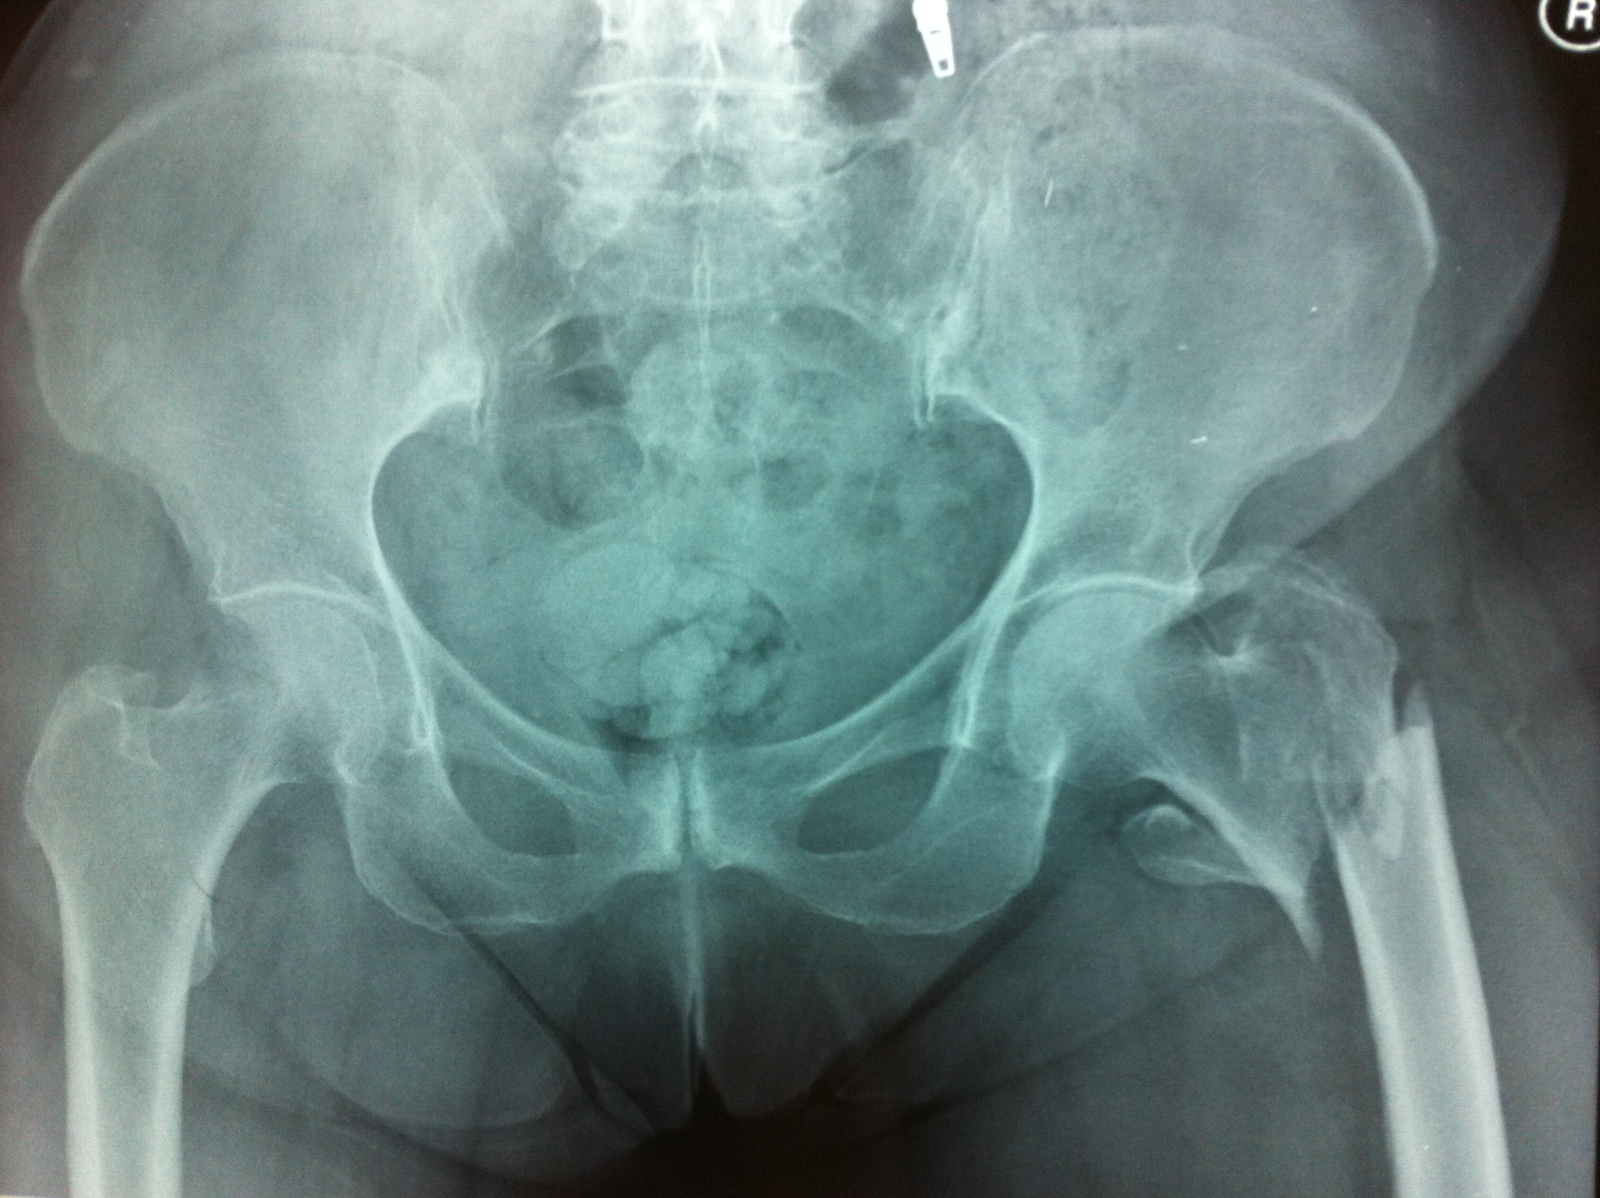

Osteoporotik zeminde gelişen kalça kırığı

• Kamburluk